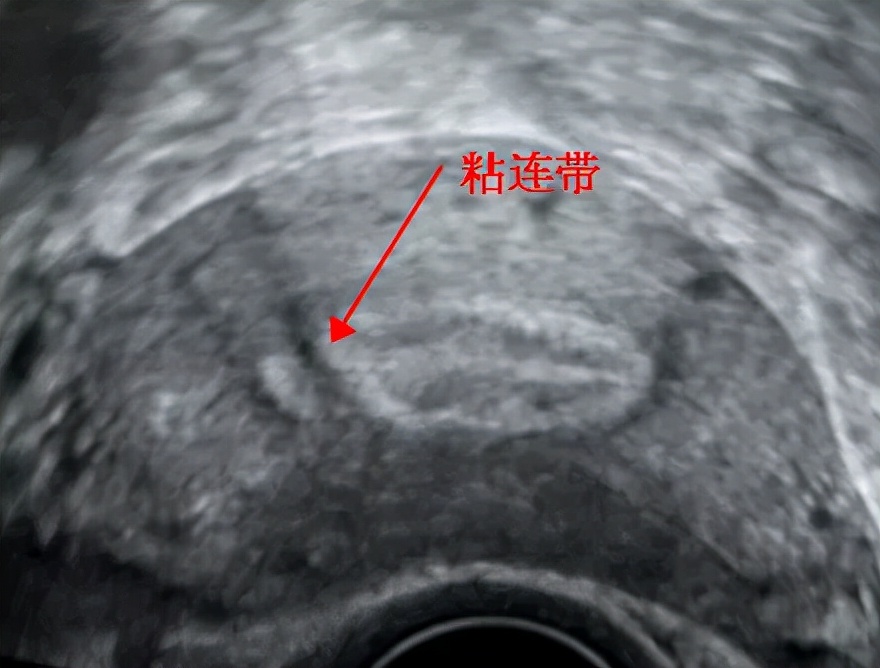

内膜本该连续的地方却见到一处连续性中断的地方

箭头所指就是粘连处